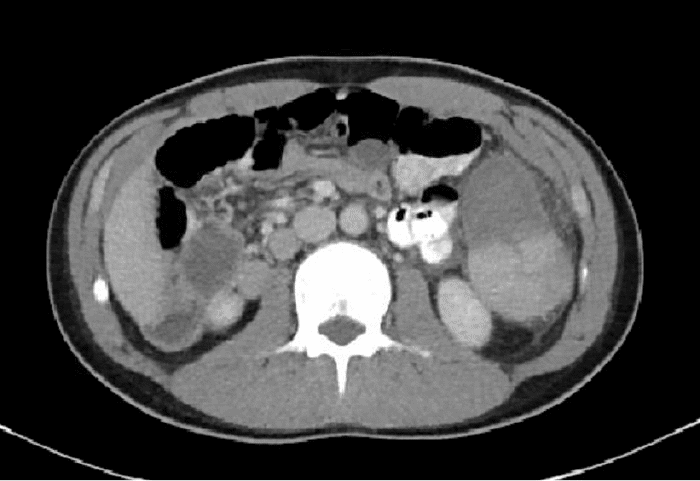

An abnormal twisting configuration, known as the "swirl sign," was observed in the left-upper to mid-abdominal mesentery, leading to the presence of a very large accessory spleen measuring 14 × 5 × 6 cm. This accessory spleen was partially vascularized and situated adjacent to the gastric wall, with its superior aspect being nonvascular (Figure 2). Notably, prominent inflammatory stranding surrounding the mesentery was also identified. The patient was determined to have a large accessory spleen with volvulus, resulting in an infarction or injury (Figure 3).

Figure 2. Abdominopelvic CT Scan. Published with Permission